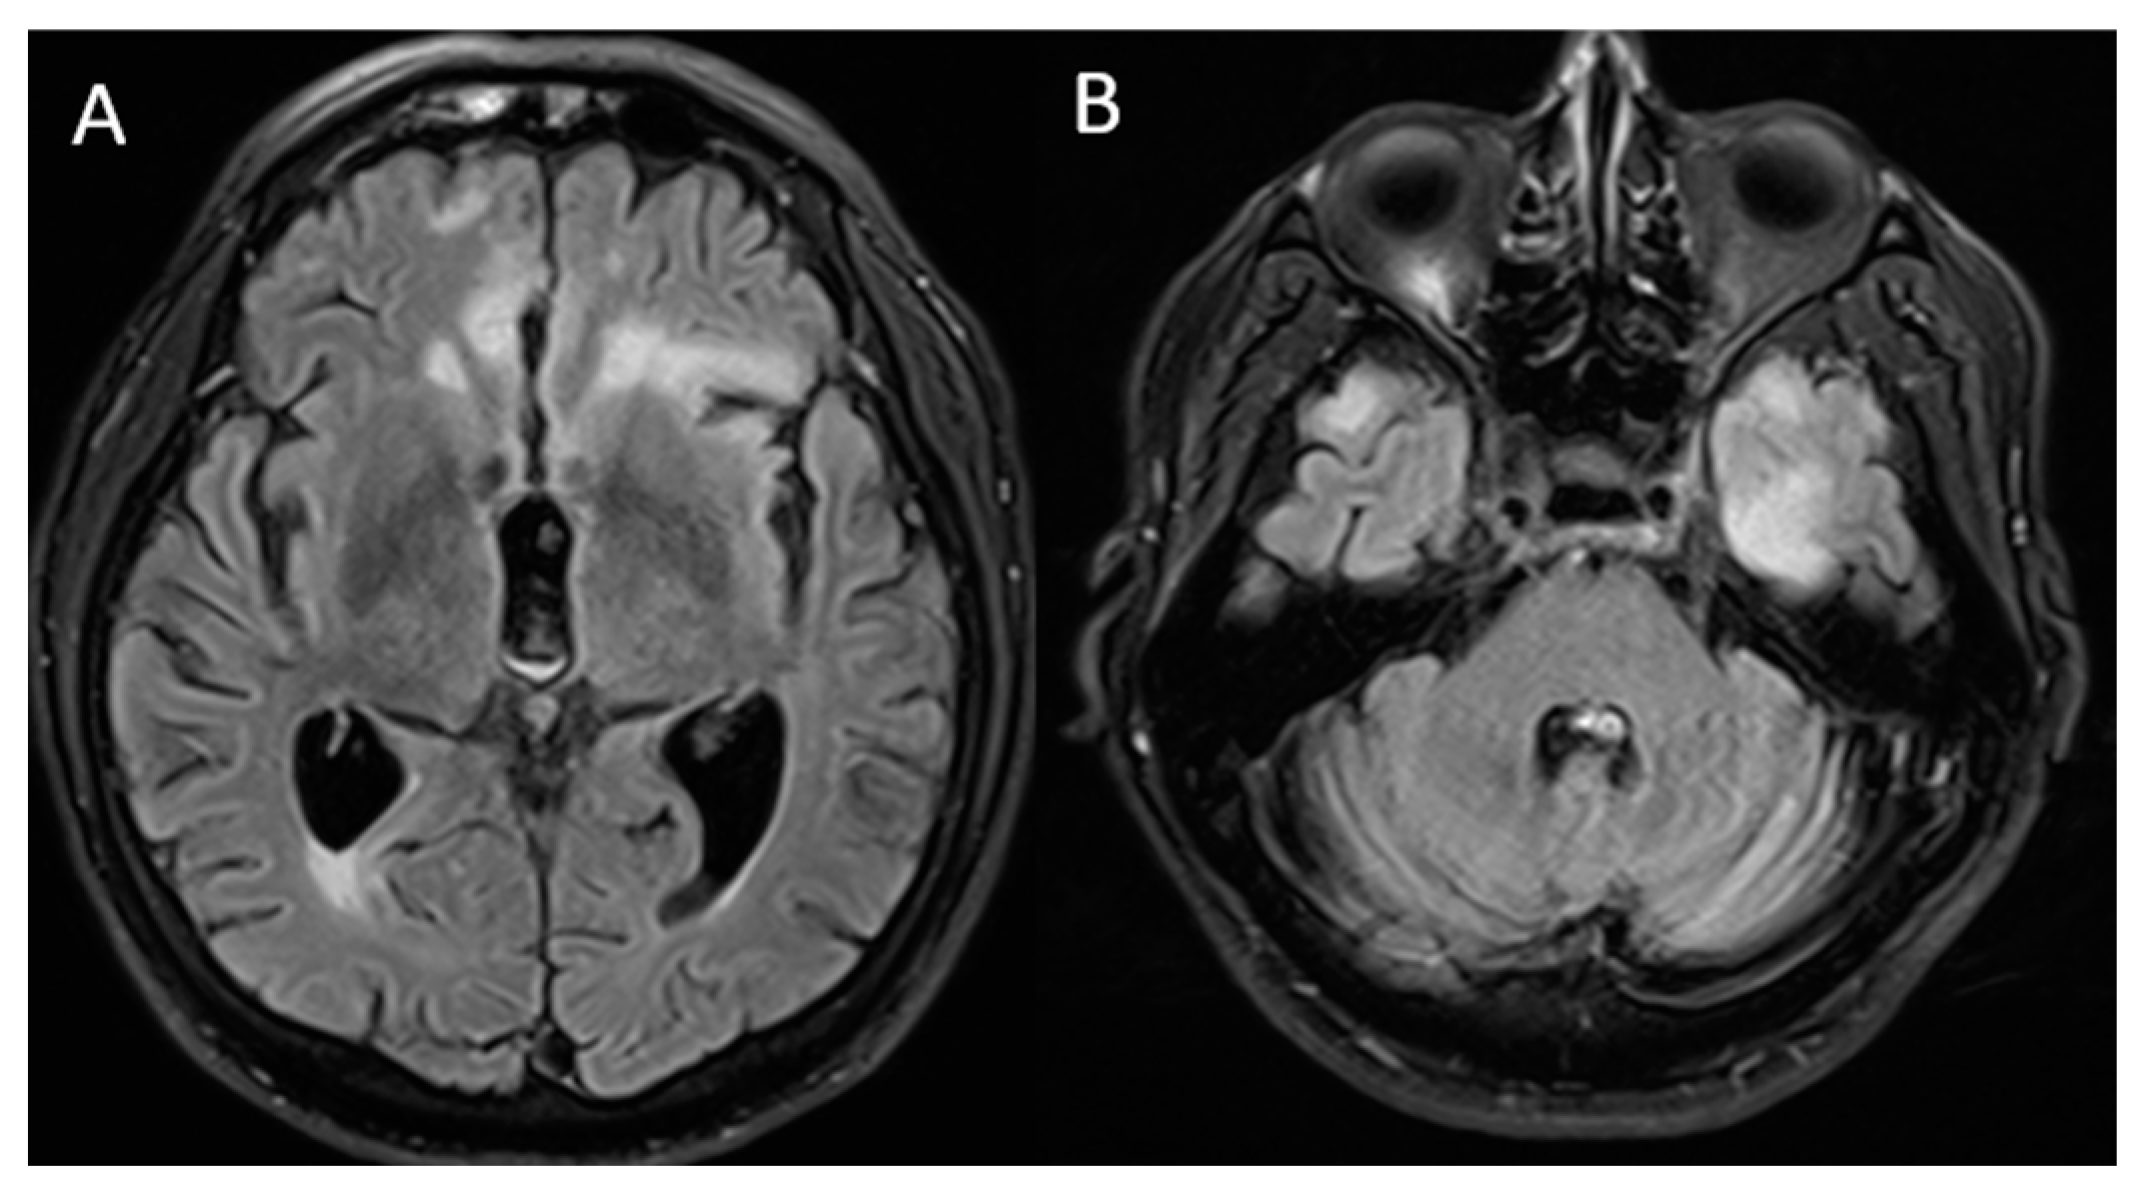

| Vences M.A. (2022) In this study | 72 (Male) | High blood pressure and diabetes mellitus | Headache, confusion, aggressiveness, instability | Not performed | Elevated protein levels | mRNA (Pfizer) and two doses | 1st dose: 1 day and 2nd dose: 4 days | MRI: bilateral frontal and insular hyperintensity | Yes | Methylprednisolone, intravenous immunoglobulin | Six-monthly cycles of methylprednisolone |